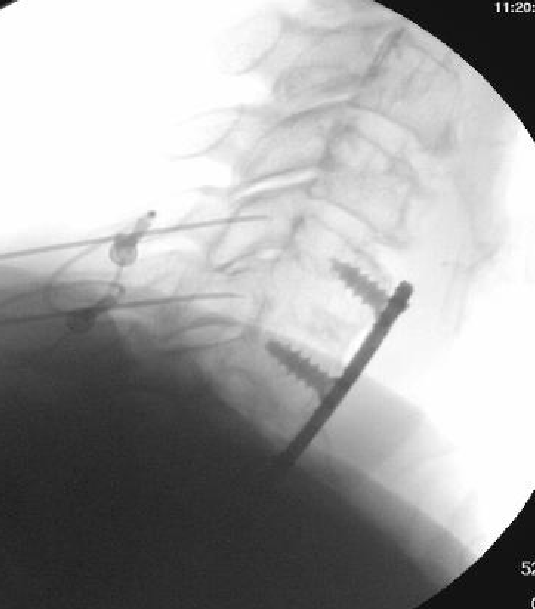

Nasty neuritis. This is 80 degrees 90 seconds.

These images look great. Sorry it happened? Steroid?

Lyrica Rx sent in, and we're starting it for chronic pain (and neuritis). She gets a shoulder scope in two weeks for a large RCT. I like antineuropathics (gabapentin 100mg HS or BID) perioperatively in general. I wish they were given 2 weeks before and after ALL orthopedic surgeries.

Dexamethasone given before RFA needles were removed.